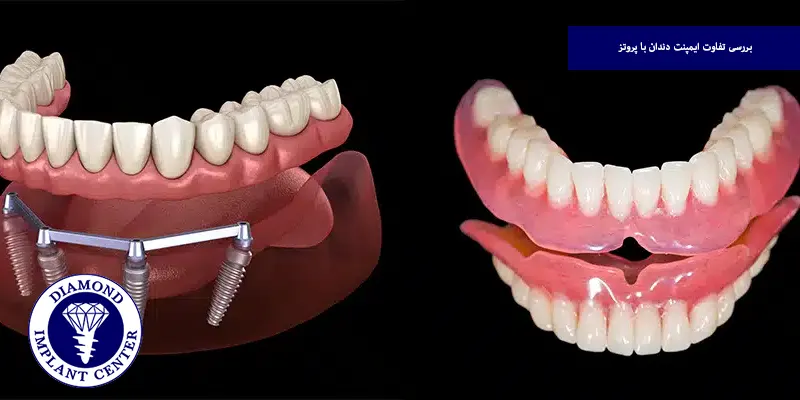

وقتی دندان های خود را از دست میدهیم، اولین سوال این است که بهترین روش جایگزینی دندان کدام است؛ ایمپلنت یا پروتز؟ بسیاری افراد بین این دو روش مردد میمانند، چون هرکدام مزایا، معایب و هزینه های خاص خود را دارند، ایمپلنت به عنوان یک روش دائمی و مقاوم شناخته میشود، در حالی که پروتزها بیشتر به دلیل قیمت مناسب و دسترسی آسان مورد توجه قرار میگیرند، اما کدام گزینه انتخاب بهتری برای شماست؟ ماندگاری و زیبایی ایمپلنت ارزش هزینه بالاتر را دارد یا پروتز همچنان یک راهحل کاربردی است؟

ایمپلنت دندان به دلیل اتصال مستقیم به استخوان فک و جنس مقاوم تیتانیومی، معمولا ماندگاری بسیار بالایی دارد و در صورت رعایت بهداشت دهان ۱۰ تا ۲۰ سال یا حتی بیشتر دوام میآورد و در مقابل، پروتزهای دندانی به ویژه نوع متحرک، استحکام و طول عمر کمتری دارند و هر ۵ تا ۷ سال نیاز به تعویض یا تنظیم پیدا میکنند، به همین دلیل، از نظر دوام و ماندگاری، ایمپلنت انتخاب مطمئن تر و طولانی مدت تری نسبت به پروتز محسوب میشود.

از نظر زیبایی، ایمپلنت دندان شباهت بسیار زیادی به دندان طبیعی دارد، زیرا به طور مستقیم در استخوان فک قرار میگیرد و تاج آن به طور هماهنگ با سایر دندان ها ساخته میشود، این موضوع باعث میشود لبخند طبیعی تر و هماهنگ تر به نظر برسد، در مقابل، پروتزهای متحرک یا حتی برخی پروتزهای ثابت در اثر گذر زمان تغییر رنگ میدهند، لبه های فلزی آنها نمایان شده یا به دلیل تحلیل استخوان و لثه دچار فاصله و ناهماهنگی میشوند، به همین دلیل، ایمپلنت در درازمدت زیبایی و هماهنگی بیشتری نسبت به پروتز فراهم میکند.